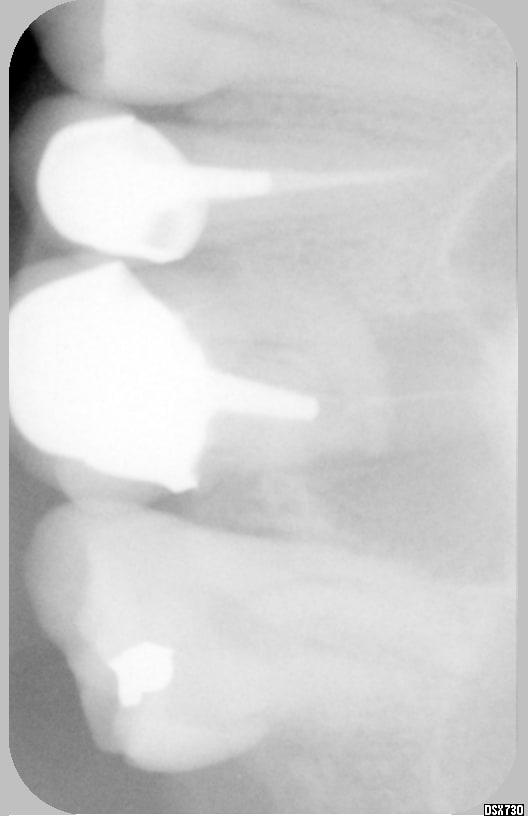

ton canal, il est pas coudé à 90° mais à 45° avec une seule courbure. ça ne devrait pas poser de problème, si tu y vas doucement avec une bonne cavité d'accès, et sans forcer. d'autant que même si la radi est pourrite, on ne voit pas trace de l'ombre d'un badigeonnage dudit canal.

j'ai regardé ta radio a tete reposée (sur l'oreiller car elle est couchée sur le flanc ta radio), de toute manière tu vois quoi a part dépose et retraitement?

on voit pas trop bien à la radio ,mais le canal mésial semble calcifié tu peux essayer quand même